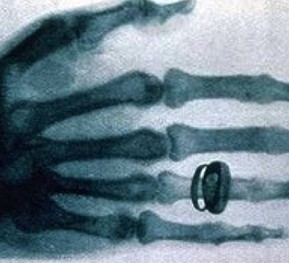

X光机主要是由X光机电源,X光球管以及控制电路等组成,是产生X光的设备,目前已广泛应用于医院协助医生诊断疾病,工业的无损探伤,科学教育,机场和火车站的安全检查等

图像监控法是直接从x射线透视图像构形来判断物品的,因此,被检物是否可疑,取决于监视器或显示器上的图像。显示器或监视器上出现的不常见物或异形物,都应视为可疑物品。那些不能准确辨认的物品也应视为可疑物品,需仔细观察,根据需要可将图像定位分析。